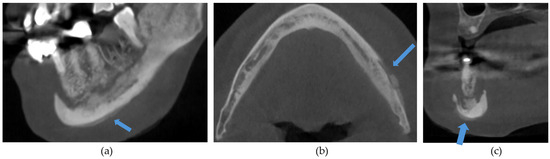

The CBCT findings commonly observed in patients with MRONJ are osteosclerosis, osteolysis, periosteal reaction, and sequestration [13,14,15,16,17,18]. The histomorphological analyses of MRONJ lesions have revealed three distinct patterns: (1) prominent bone resorption in regions of active inflammation, (2) acellular necrotic sequestra with large Haversian canals, and (3) increased inter-osteonic bone deposition with smaller Haversian canals and trabecular thicknesses in non-necrotic regions [19]. Abnormal bone remodellling characterised by reduced osteoclastic activity and increased appositional osteogenesis contributes to the radiological pattern observed in MRONJ lesions. In earlier stages of MRONJ, non-healing extraction sockets, the thickening of lamina dura, and periodontal ligament (PDL) space widening may also be observed [14,16,18,20]. In maxillary MRONJ, more prominent maxillary sinus mucosal thickening can be observed, although no significant differences in sinus volumes have been noted [21]. These radiological manifestations are illustrated in Figure 1, Figure 2, Figure 3, Figure 4 and Figure 5.

Figure 4. (a) Sagittal, (b) axial, and (c) coronal sections demonstrating a periosteal reaction (arrows) in the right posterior mandible.